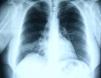

Em Junho de 2007 inicia queixas de tosse com expetoração mucosa escassa e pieira. Ao exame objetivo, de salientar sibilância à auscultação pulmonar na metade inferior do hemitórax direito, sem sinais de dificuldade respiratória ou outras alterações de relevo. Realizou radiografia torácica que mostrou hipotransparência de forma triangular no terço inferior do campo pulmonar direito (fig. 1). Complementou estudo imagiológico com TC torácica que revelou atelectasia do lobo médio e imagem nodular no brônquio lobar médio com cerca de 6mm (fig. 2). Analiticamente apresentava hemograma, ionograma, função hepática e renal sem alterações. As provas funcionais respiratórias revelaram síndrome obstrutiva ligeira. Realizou broncofibroscopia que mostrou formação tumoral na entrada do brônquio lobar médio, muito vascularizada, causando obstrução total deste (fig. 3). Não foi realizada biopsia da lesão pelo aspeto morfológico sugestivo de tumor carcinoide e pelo risco de hemorragia associado. A doente foi então submetida a broncoscopia rígida, sendo efetuada biopsia da lesão, cujo estudo anátomo-patológico foi inconclusivo.